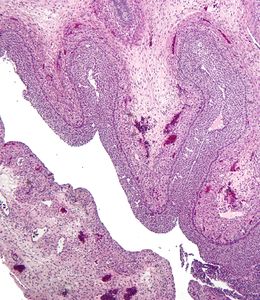

![]() 显微镜下的黄体化卵巢滤泡性囊肿 |

这类疾病发生于未发生排卵的情况,滤泡没有及时破裂或者排出,而继续生长直到形成囊肿,或者一个成熟卵泡消失。它通常形成于排卵期,可以生长到直径超过7厘米。囊肿呈薄壁状、链接一层或多层的粒层细胞,并充满清晰液体。